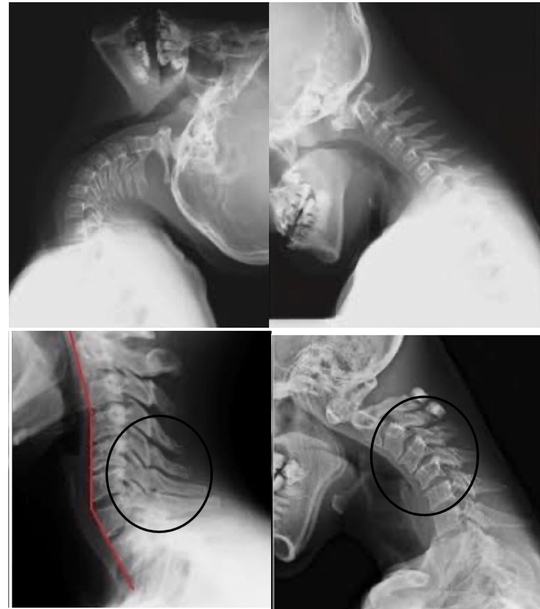

首を後ろに倒すと痛いワケ

首が上を向くときは首だけで動くことはありません。

背中の「胸椎」と連動して動きます。

だから背中の柔らかさがなくなることが上を向いた時の「痛み」の原因の1つになります。

カラダには連動性が必要なのです。

首の痛みは首だけの問題ではありません。

ストレートネックになる原因

ストレートネックはデスクワークなどで多く頭が前に出ることにより発生します。

アタマが前に出ると首への負荷が高まり、筋の緊張はドンドンドンドン高まっていきます。

当然、デスクワークなどは首だけの問題ではなく、姿勢の問題も大きく関与してきます。